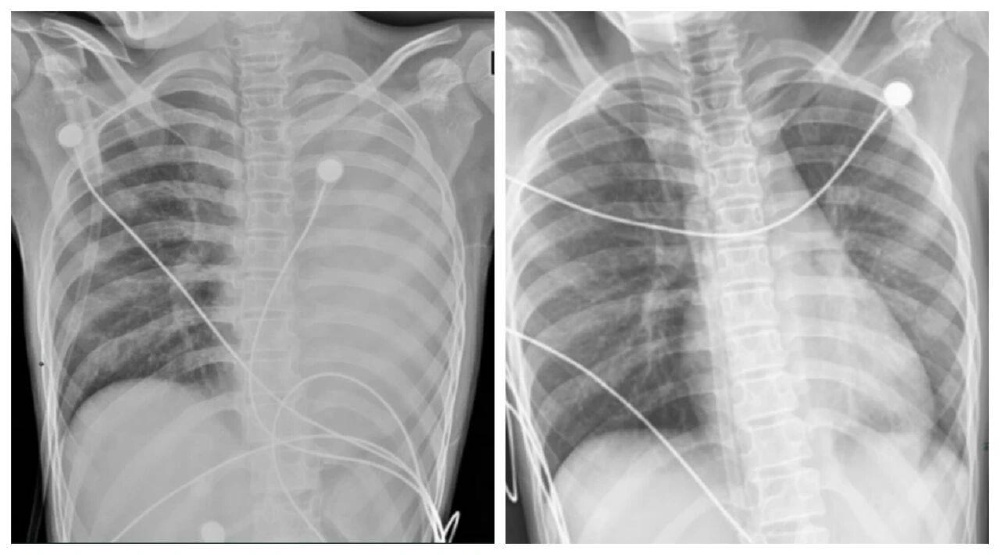

▲笑笑治疗前,左肺呈“白肺”状态,治疗后“白肺”被吸收,心脏边缘清晰可见。图源:浙大四院

一开始,她只是轻微咳嗽,发热后在外院检查提示肺炎、肺不张,转诊到浙大四院儿科时,笑笑出现呼吸急促、胸闷胸痛,血氧饱和度勉强维持在90%左右,胸片显示左肺已完全呈“白肺”改变,病情急剧恶化。

术后第二天,笑笑呼吸困难、胸痛的症状明显好转,病情得到了初步控制。经过精准抗感染、祛痰、抗炎等系列治疗,笑笑逐渐康复,顺利出院。